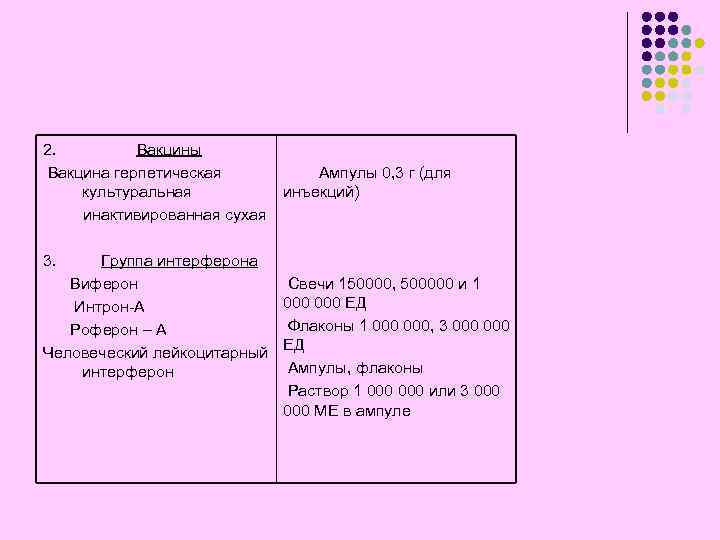

2. Вакцины Вакцина герпетическая культуральная инактивированная сухая 3. Ампулы 0, 3 г (для инъекций) Группа интерферона Виферон Свечи 150000, 500000 и 1 000 ЕД Интрон-А Флаконы 1 000, 3 000 Роферон – А Человеческий лейкоцитарный ЕД Ампулы, флаконы интерферон Раствор 1 000 или 3 000 МЕ в ампуле

2. Вакцины Вакцина герпетическая культуральная инактивированная сухая 3. Ампулы 0, 3 г (для инъекций) Группа интерферона Виферон Свечи 150000, 500000 и 1 000 ЕД Интрон-А Флаконы 1 000, 3 000 Роферон – А Человеческий лейкоцитарный ЕД Ампулы, флаконы интерферон Раствор 1 000 или 3 000 МЕ в ампуле